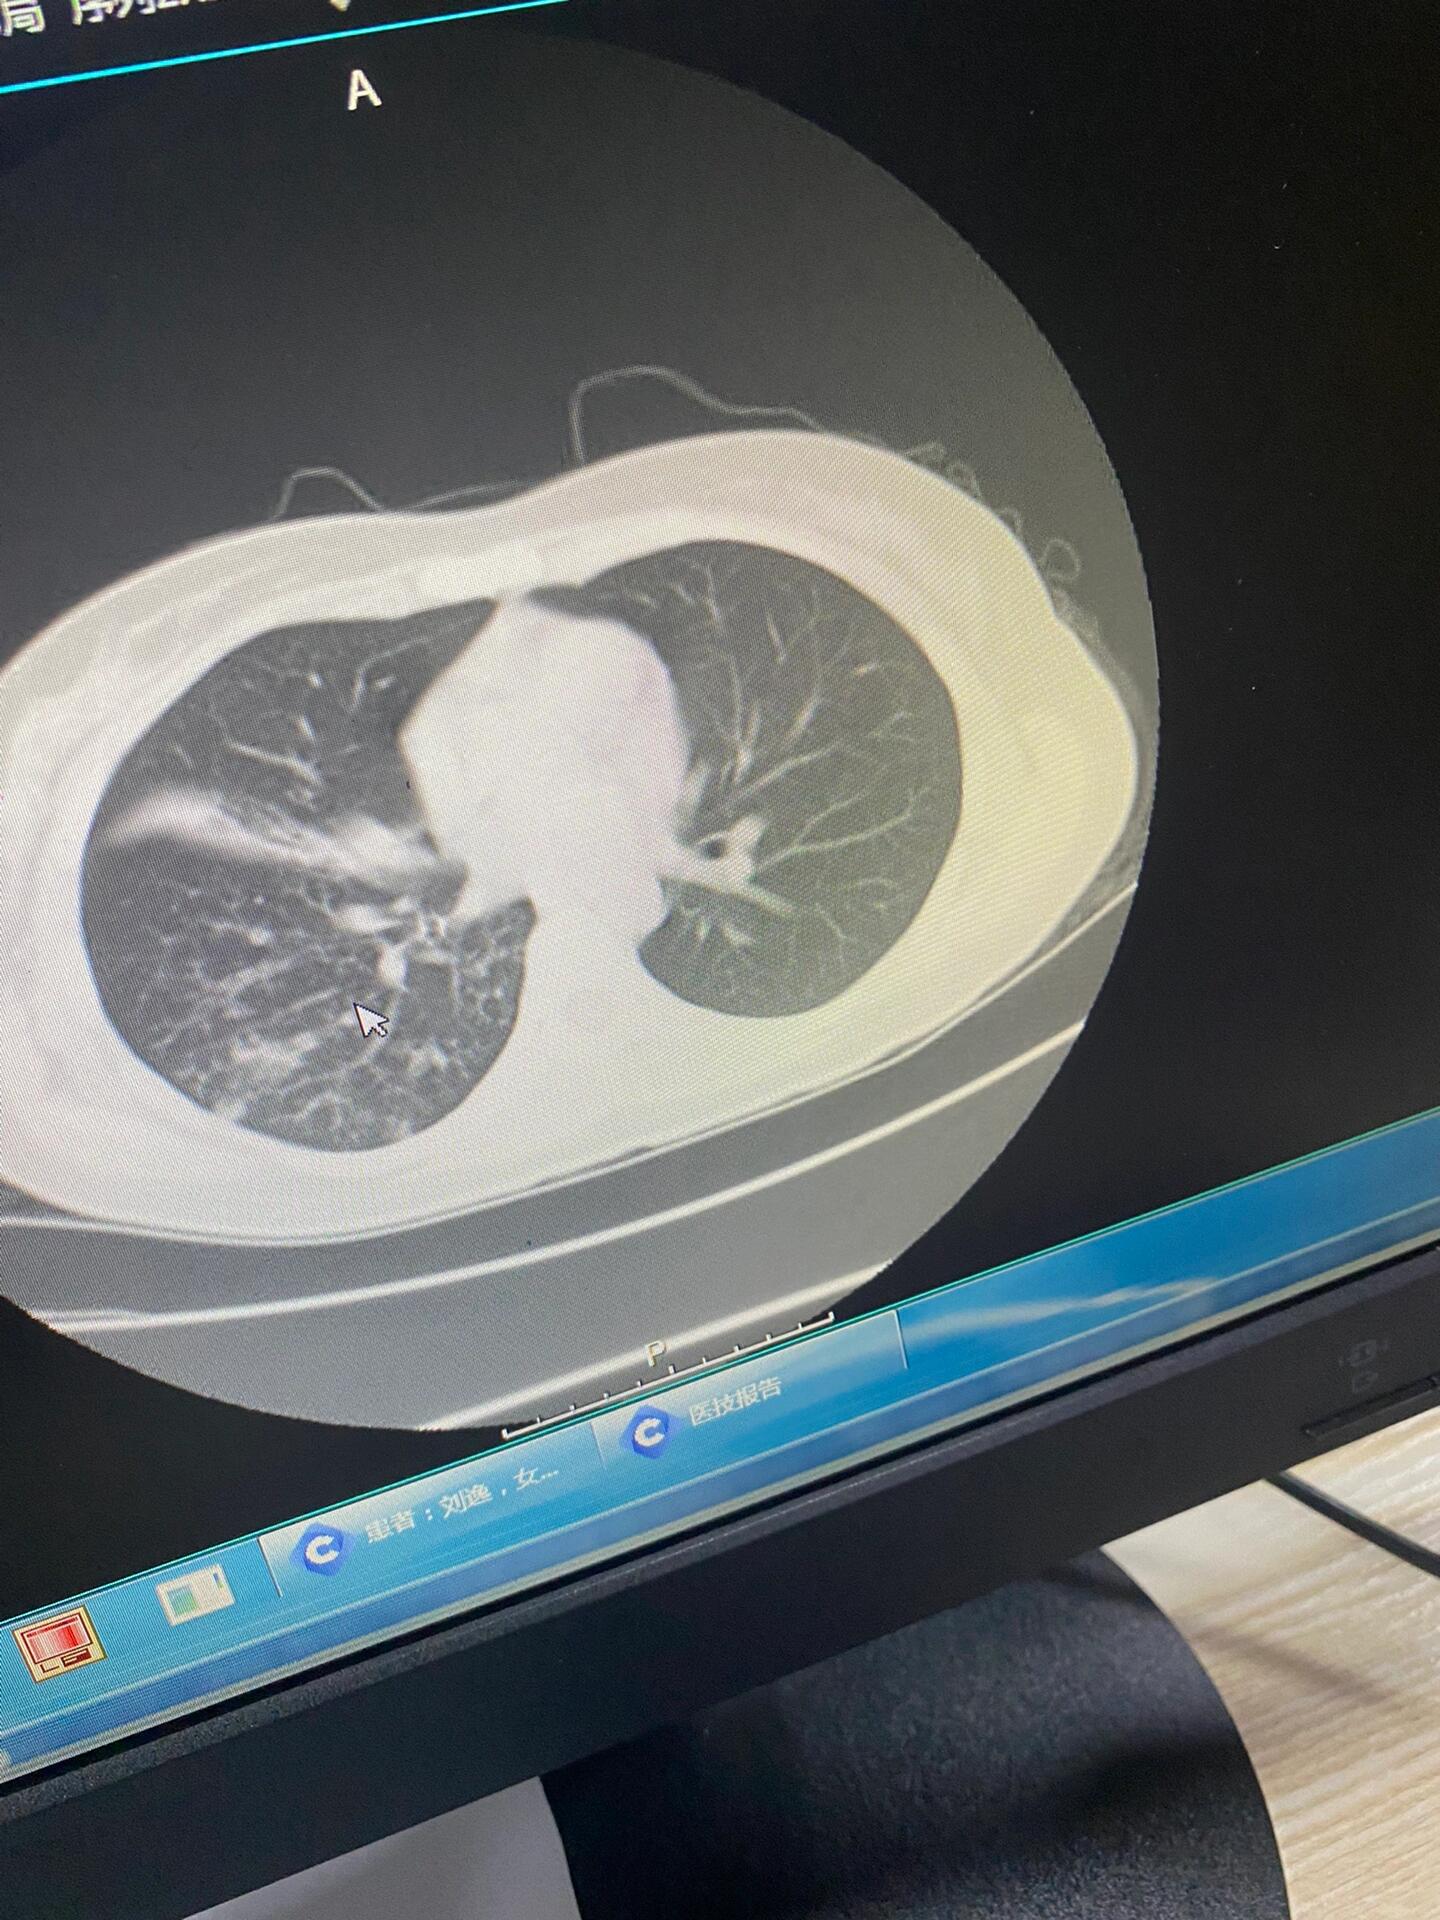

在X线表现可以出现斑片状阴影,如果出现空洞,比较严重因为空洞中可以出现细菌感染,可以引起咯血呼吸功能衰竭如果合并咯血,病情相对严重,传染性比较强,可以引起疾病传播但是结核病是一种可以治疗的疾病,发现空洞以后应该积极治疗经过抗结核治疗,大部分的肺结核包括合并空洞的病人均可治好。

由于肺部是气体交换的核心器官,空洞的存在会进一步干扰整体通气效率,可能引发呼吸功能受限,表现为活动后气促低氧血症等症状常见病因与疾病关联引发肺部空洞的疾病多与感染或肿瘤相关,其中肺结核肺脓肿和肺癌最为典型肺结核由结核分枝杆菌感染引起,空洞壁常伴有干酪样坏死,具有传染性,需长期抗。

肺结核空洞形成后的严重程度可以根据造成的不同结果进行判断,大部分空洞在形成后随治疗会慢慢缩小,部分空洞会塌陷闭塞,所以空洞一般不会导致危险但有部分空洞可以存在其它新生物长出,甚至曲霉菌感染,往往随真菌感染侵袭性感染后把空洞壁毛细血管甚至小动脉腐蚀,形成咯血,此类型存在危险因素空洞。